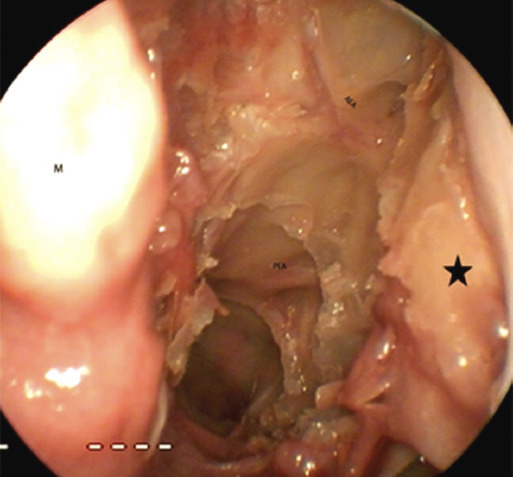

Method: Five fresh frozen cadaveric heads underwent computed tomography and endoscopic sinus surgery. The lateromedial length of the anterior ethmoidal artery (AEA) and its distance to the axilla of the middle turbinate (MTA), the sphenoethmoidal recess (SR) and the posterior ethmoidal artery were measured. The posterior ethmoidal artery (PEA) was referenced to the SR. These anatomical parameters were measured both radiologically and endoscopically, and the compatibility of the two was examined.

Results: Ten nasal cavities were dissected. We found that the distance of MTA to the AEA was 16±8 mm in dissection, 21±4 mm radiologically in the sagittal section, the distance of SR to the AEA was 14±3 mm in dissection, 19±4 mm radiologically in the sagittal section, and the distance of the AEA to the PEA was 10±3 mm in dissection, 12±3 mm radiologically in the axial section. The distance of the PEA to SR was 6±3 mm in dissection, 8±2 mm radiologically in the sagittal section.